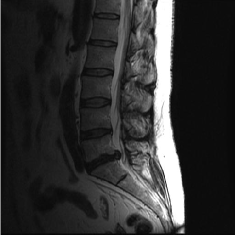

(d) Circle of Willis

Figure 2: Test Images.

We turn now to test TDIHT for high dimensional signals. We test the performance of several MRI images: the Shepp-Logan phantom, FLAIT brain image, T2 Sagittal view of the lumbar spine and the circle of Willis. The first image is of size 256×256256256256\times 256, while the other are of size 512×512512512512\times 512. They are all presented in Fig. 2.